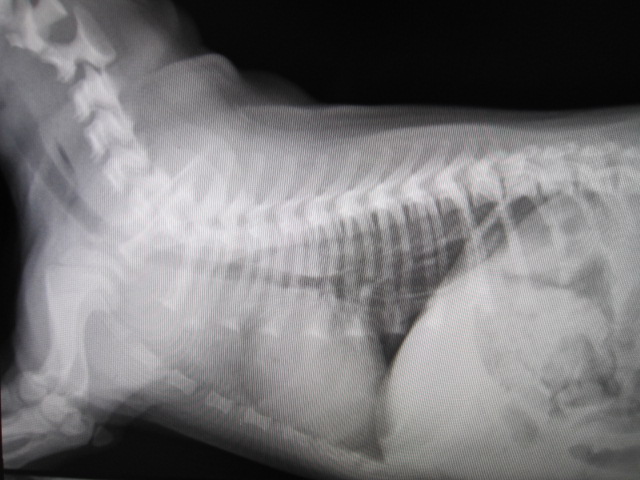

内視鏡で砂ぎもを胃に押し込みました。

食道内に異物はなくなっています。

術後

術後のレントゲンです。

食道内異物はなくなりました。